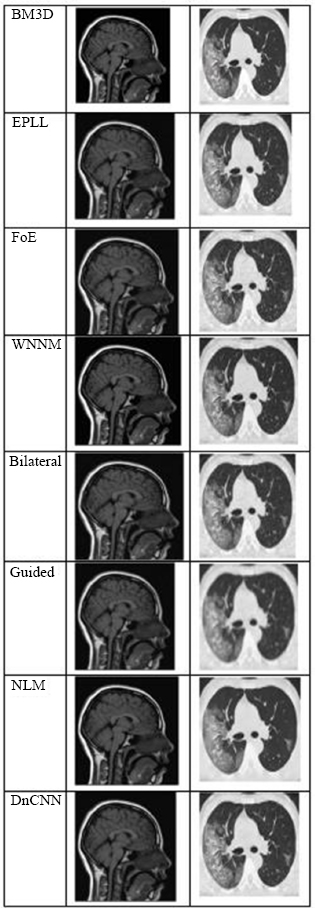

Fig. (4) shows the results at a noise variance of 0.01, where it has been observed that all algorithms produce clear images, except for the Guided algorithm.

Fig. (5) shows the results at a noise variance of 0.05, where it has been observed that the BM3D, EPLL, and WNNM algorithms produce clearer images compared to other algorithms. NLM and DnCNN also perform well, but not as well as the above-mentioned three algorithms.

Fig. (4).

The output of different algorithms at a noise variance of 0.01.

Fig. (5).

The output of different algorithms at a noise variance of 0.05.

Fig. (6) shows the results at a noise variance of 0.09, where it is observed that the BM3D, EPLL, and WNNM algorithms produce clearer images compared to other algorithms. Another algorithm, DnCNN, also performs well, but not so well as the above-mentioned three algorithms.

Fig. (6).

The output of different algorithms at noise variance 0.09.

Fig. (7) shows the results at a noise variance of 0.5, where it has been observed that all the algorithms produce blurred images, except for the BM3D algorithm. However, the results of the BM3D algorithm are not so satisfactory. As a result, it has been observed that at a noise variance of 0.5, none of the algorithms performed well.

Fig. (7).

The output of different algorithms at Noise Variance 0.50.

It has been observed that, except for the Guided Filter, which was unable to preserve edge details successfully, most algorithms presented visually clear and good results at low noise levels (variance = 0.01). Techniques such as BM3D, EPLL, and WNNM consistently produced better quality and detail preservation than others in terms of their visual quality and detail preservation at medium noise levels (variance = 0.05 and 0.09). Although their performances were commendable, those of NLM and DnCNN were slightly less accurate and reliable.

All the algorithms performed poorly at the high-noise level (variance = 0.5), producing significantly distorted and degraded images. At this level of noise, even BM3D, which had demonstrated relative robustness, could not produce outputs appropriate for diagnosis. This result highlights the limitations of current denoising methods in high-noise or low-SNR conditions that are common in low-dose or accelerated medical imaging scenarios.

4.7. Clinical Impact After Denoising

To demonstrate the clinical importance of denoising, a comparison is made between noisy and denoised sagittal T1-weighted MRI images. The noisy image may be difficult to diagnose due to its grainy texture and low contrast of tissue structures, as significant structures, such as the brain stem, thalamus, and corpus callosum, are obscured. These make a lot more sense post-denosing, enabling the assessment of subcortical integrity, the inspection of ventricular pathways, and the secure differentiation of gray and white matter. These improvements are not limited to visual interpretation; their direct application to early detection and treatment planning of diseases such as hydrocephalus, multiple sclerosis, and brain tumors firmly places them within the medical field.

To highlight the clinical significance of denoising, a comparison is performed of the visual and anatomical enhancements visible in high-resolution chest CT images. In the initial HRCT model with noise, the clarity of the bronchial walls, pulmonary vessels, and interstitial markings was greatly affected by high-frequency noise, which is important for the identification of certain lung diseases, such as fibrosis, bronchiectasis, or pulmonary infections. Following the denoising process, restored soft tissue contrast and improved visualization of segmental bronchi, vascular branches, and pleural boundaries were observed in the resulting image. Such improvements have a direct impact on the confidence of radiologists, the predictability of lesions, and the probable reduction of false diagnoses. Accordingly, technical validation using PSNR and SSIM was achieved, while the clinical advantage of the denoising procedure was demonstrated by the preservation of diagnostically important structures crucial for accurate thoracic interpretation.